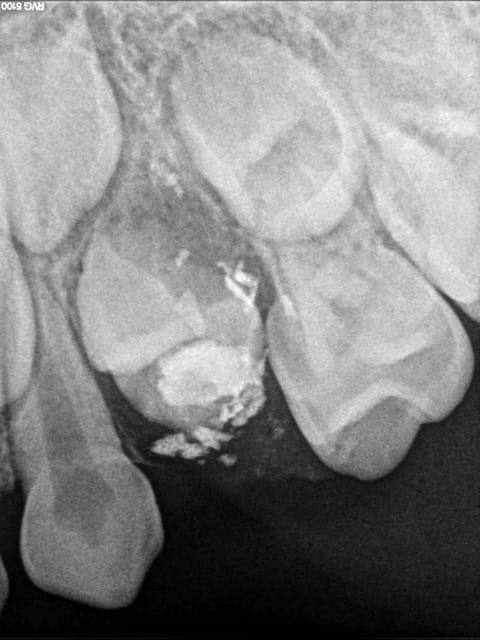

J'ai fait un traitement canalaire sur la 64 à une gamine de 4 en 2010, je la revoie hier soit 18 mois après le soin. la gamine avait la dent à la main. j'ai pensé que la dent s'est cassée, mais en fait il reste plus rien. la dent à l'origine était infectée, j'ai alésé, nettoyé, obturé dans la séance. j'ai utilisé le sealite comme pâte d'obturation pour la pérennité pendant au moins 5 ans. Mais au bout de 18 mois tout a disparu. Que s'est il passé? merci

Le germe de 24 n'a pas l'air indemne non plus... Serait -il pas entrain de disparaître aussi ?

(je me demande ce qui apparaît sur la post-op, c'est comme si du ciment avait fusé dans le sac pericoronaire)

Sur la radio post-op, on voit un gros dépassement de pâte qui coiffe le germe de la dent définitive, juste à l'endroit où sur la deuxième il semble y avoir un problème...

et dire que sousou s'est fait chier a faire un tr avec digue et tout le tralala sur un mouflet de 4 ans, tout ça pour y bouziller le germe sous-jacent!

je salue le courage de l'intention (une endo+digue sur un si petit! chapeau bas!), mais pas de bol sur le dépassement massif (c'était quoi la technique d'obturation?)

Faut pas chercher + loin: la pâte qui a fusé à la perif' du germe a simplement détruit les cellules formatrices...